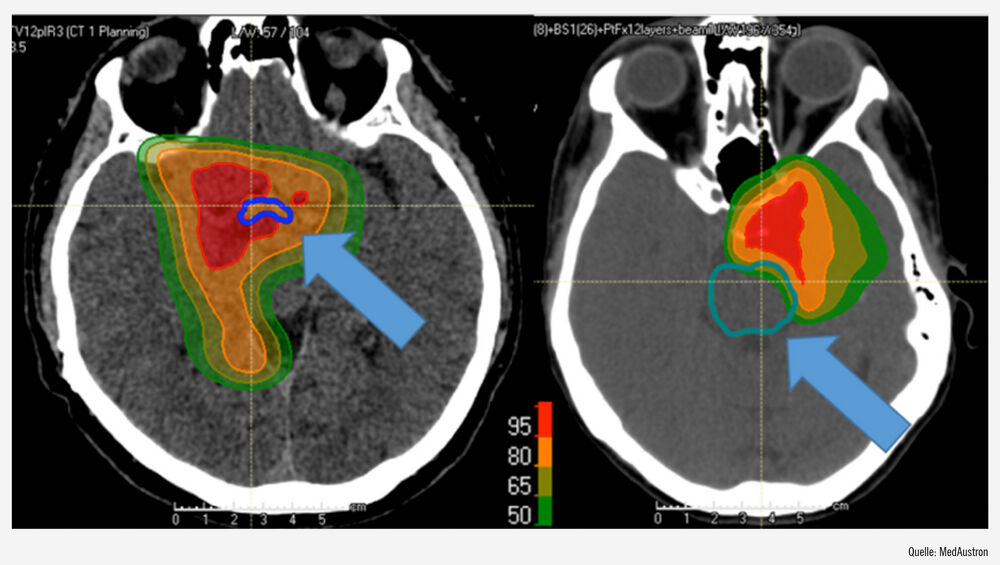

Der physikalische Vorteil von Protonen gegenüber Photonen wird auch im Bereich des ZNS und der Schädelbasis besonders tragend, da Tumoren in diesem Bereich oft in anatomischer Nahebeziehung zu kritischen, strahlensensiblen Normalgewebsstrukturen wie z. B. Hirnstamm oder zum optischen Apparat stehen (Abb.). Therapiebedingte Langzeitfolgen bei Photonenbestrahlung können neben neurologischen und/oder kognitiven Veränderungen auch die Induktion von Zweitmalignomen sein. Diese chronischen Nebenwirkungen können in einer Verminderung der Lebensqualität der individuellen Patient:innen resultieren und darüber hinaus das Gesundheitssystem erheblich belasten. In dieser Patientengruppe konnte bei MedAustron ein Jahr nach Therapie überwiegend der Erhalt der kognitiven Funktionen (z. B. visuell-motorische Koordination, Kurzzeitgedächtnis, Wortflüssigkeit etc.) beobachtet werden. Die Analysen zeigen die Reduktion von Nebenwirkungen und das Beibehalten einer hohen Lebensqualität nach der Therapie.

Abb.: links: Isodosenverteilung in Prozent einer Meningeombestrahlung mit Protonen mit Reduktion der Dosis am Chiasma (blau); rechts: Isodosenverteilung in Prozent einer Chordombestrahlung mit Reduktion am Hirnstamm (grün)